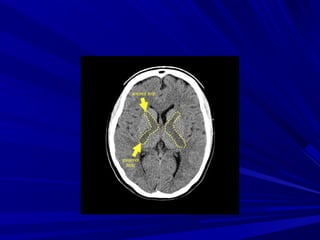

HIEÄU ÖÙNG CHOAÙN

CHOÅ

Toån thöông gaây ñaåy , eùp caáu

truùc bình thöôøng noäi soï

Hieäu öùng choaùn choå

-Caáu truùc naõo (chaát

traéng, xaùm..)

-Ñöôøng giöõa

-Naõo thaát, beå naõo,

raõnh naõo

-Maïch maùu

PHAÙT HIEÄN HIEÄU ÖÙNG CHOAÙN

Thoaùt vò naõo döôùi

lieàm

Di leäch ñöôøng